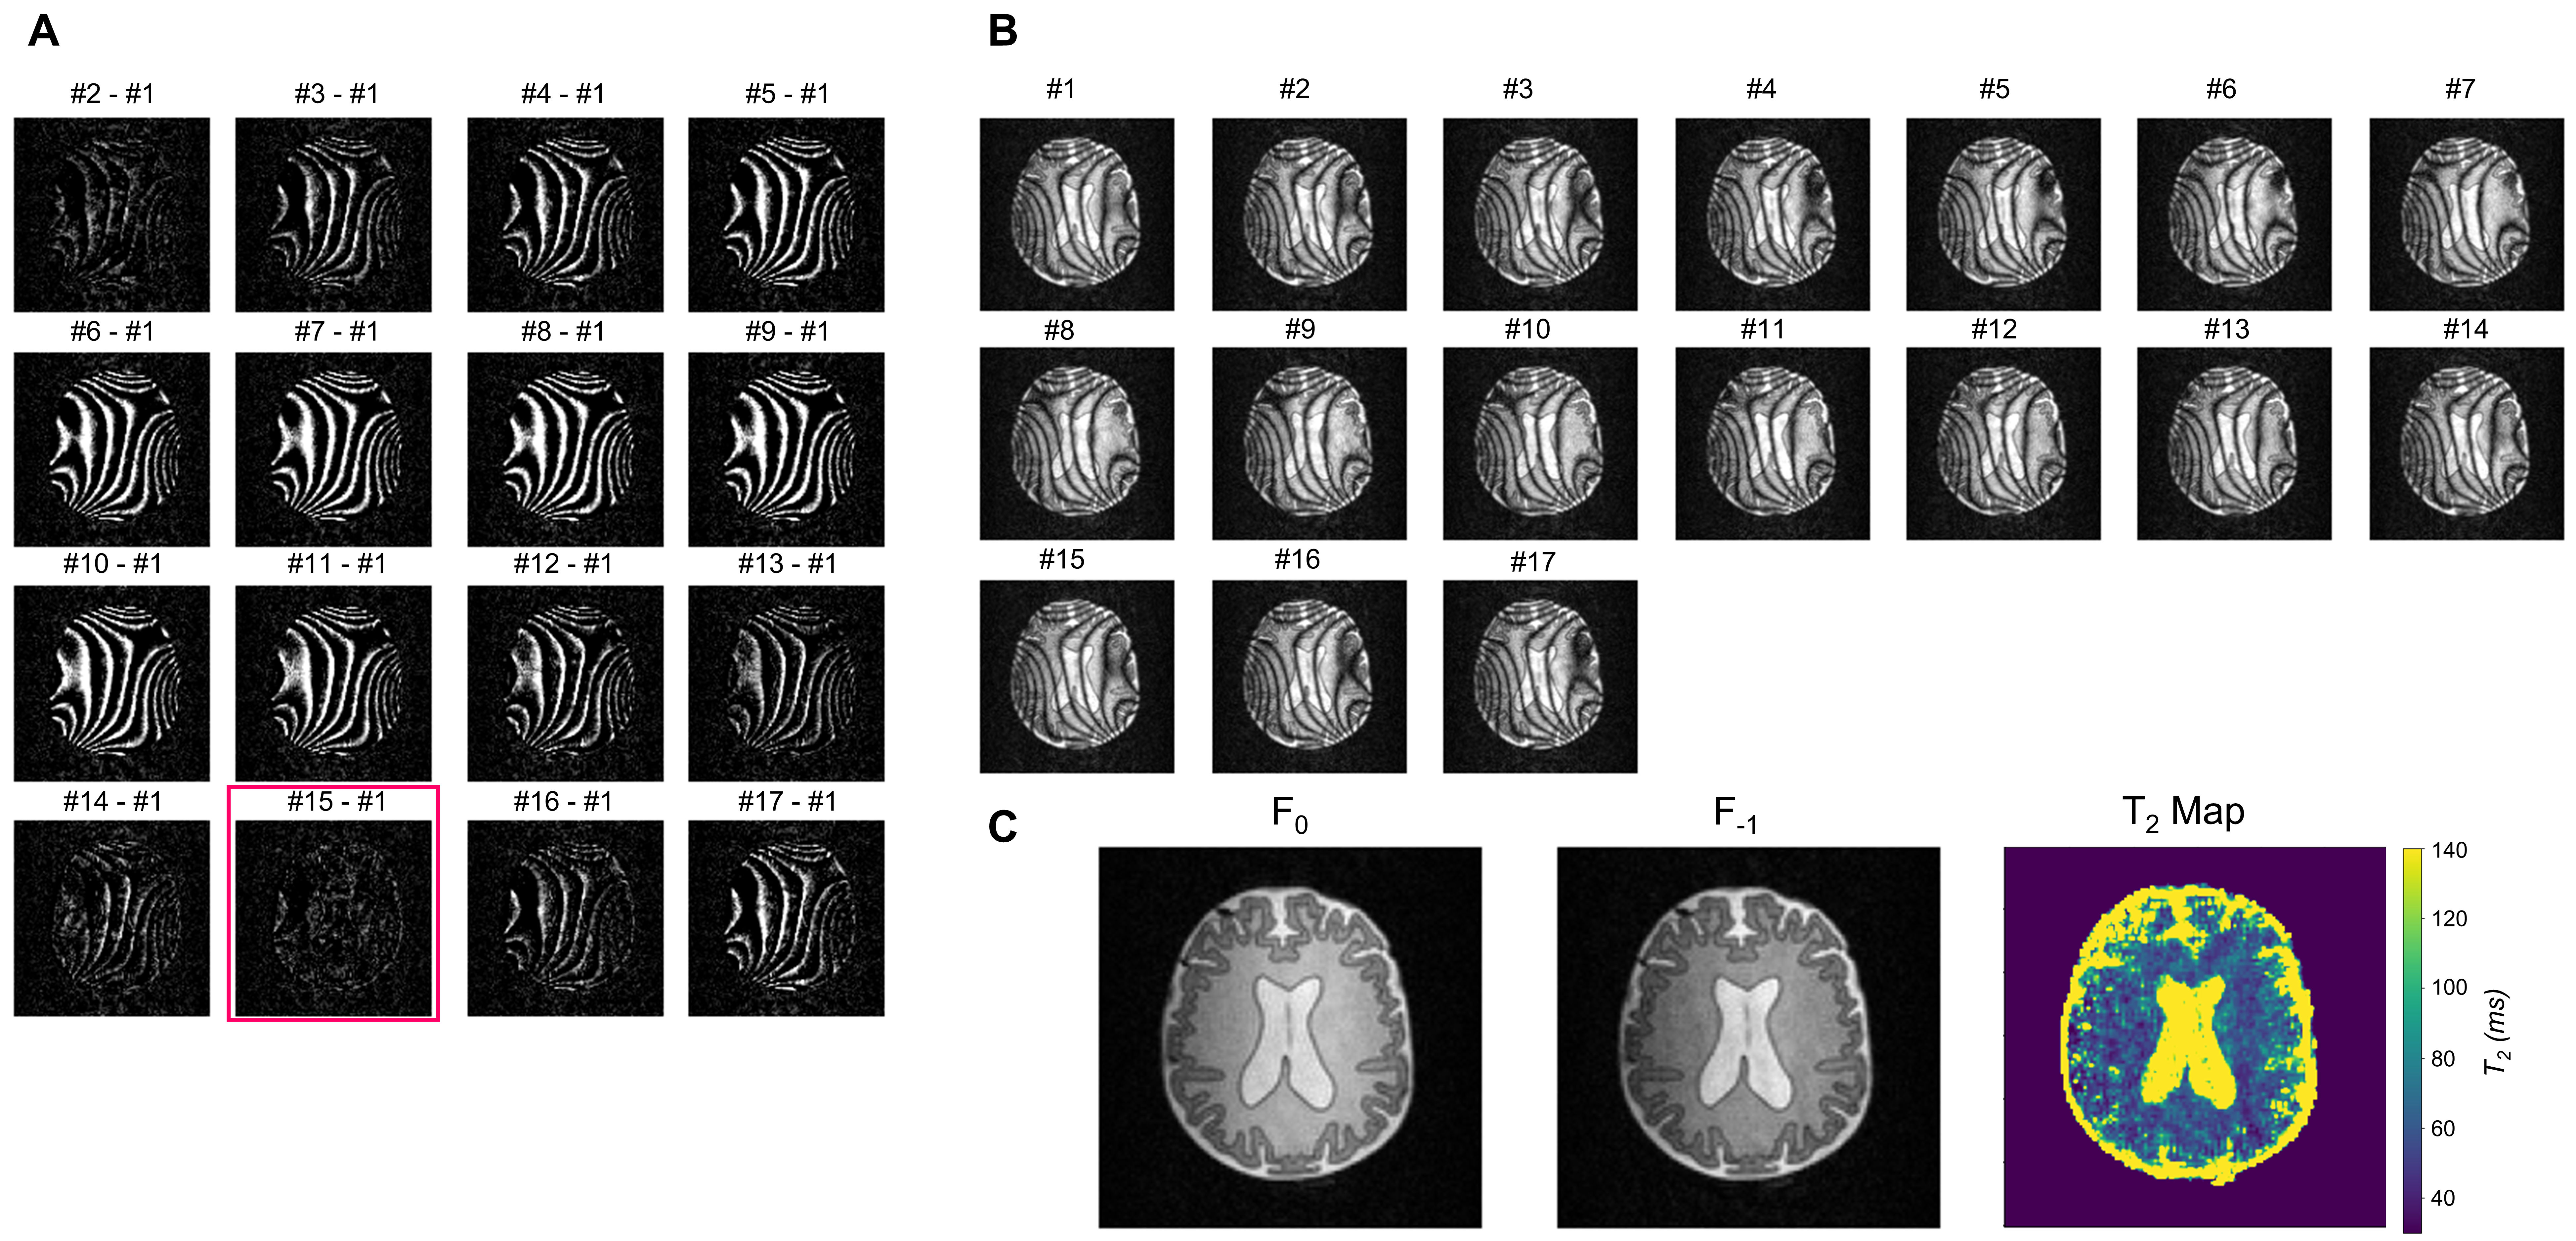

Brain-like (BrainLo) phantom: As shown in Fig.4A, GM/WM/CSF compartments had T2 and T1 values measured using conventional techniques which match in vivo values at low-field2. Slight residual banding was observed in each reconstruction, except for the maximum-intensity image (Fig.4B). The cause is probably small drifts in B0 during acquisition. By calculating the difference between each dataset and the first dataset (Fig.5A), we estimated this additional drift, corrected it and produced banding-free F0 and F-1 modes (Fig.5B), which were used to reconstruct the T2 map. The relative T2 values are in the right ratio, but absolute values in WM/GM are ~40% lower than those obtained using the much slower conventional techniques. In future experiments we will investigate whether this is a systematic error, or simply reflects the fact that different acquisition schemes result in different apparent relaxation times.

Figure 5 (A) Difference between each dataset and the first dataset (#1) was calculated to evaluate and (B) correct for frequency drift during acquisition. Data showed that image #15 was the closest to image #1 (highlighted with red square). Images #15-17 were removed from further analysis to avoid oversampling the profile for the Fourier transform. (C) F0 and F-1 modes and T2 map were reconstructed.